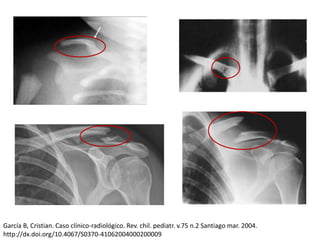

Fractura de clavicula: Clasificación de Allman Allman F L, JBJS (A) 49:774-784, 1967

García B, Cristian. Caso clínico-radiológico. Rev. chil. pediatr. v.75 n.2 Santiago mar. 2004.

http://dx.doi.org/10.4067/S0370-41062004000200009